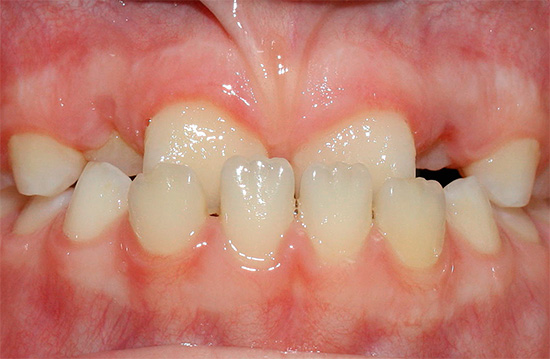

La foto mostra un esempio di un morso distale:

Nel morso distale si distinguono due sottoclassi, a seconda dell'inclinazione degli incisivi mascellari.